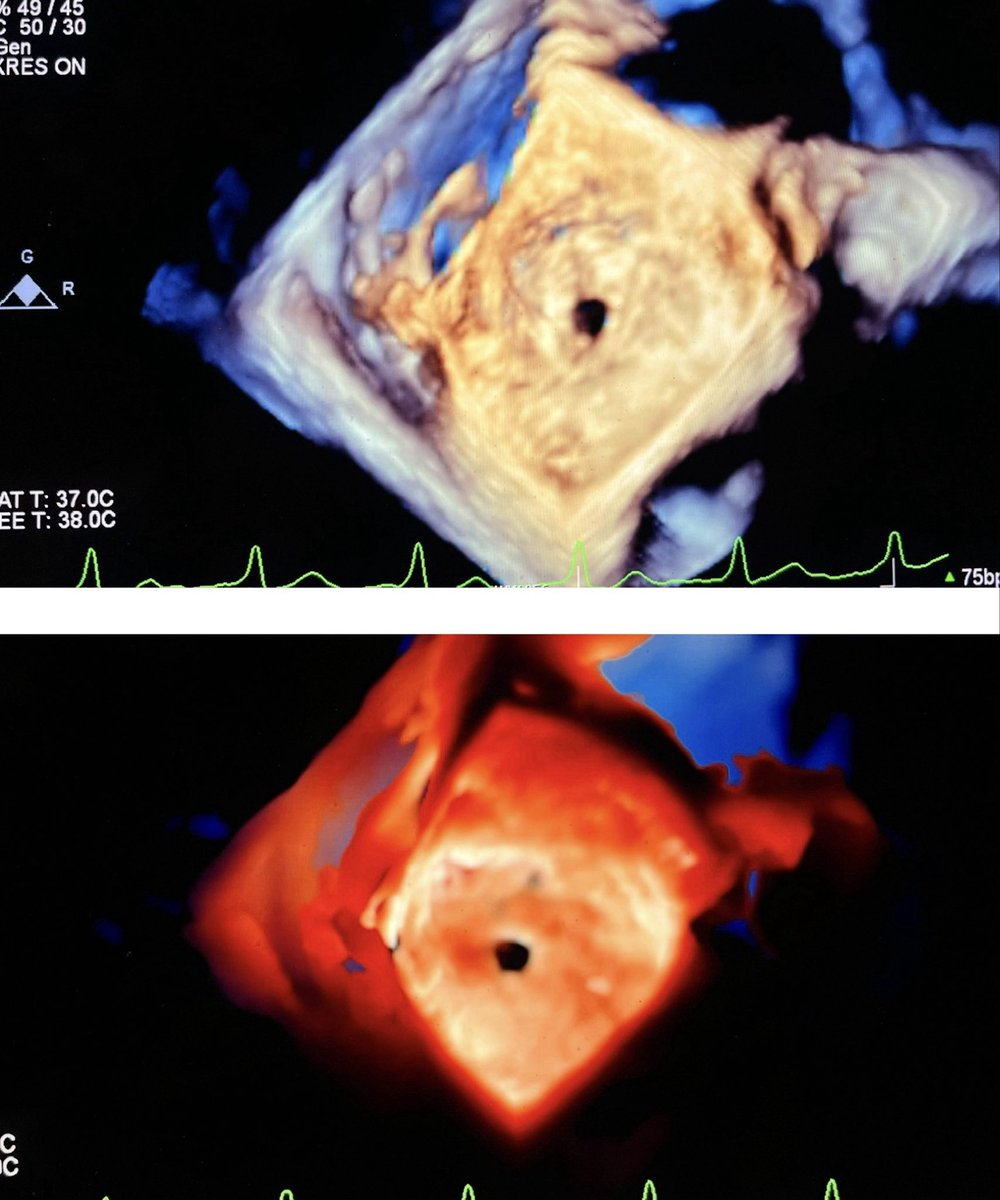

@CASivaram1

Chittur Sivaram MD MACP MACC

15 days

#echofirst ✅ For those who enjoy looking at 3D images ✅ Not a diagnostic quiz, just a sedundum ASD ⬇️ before & after device closure (Gore) @alex1708ander @OungSavly @argulian @PWesslyMD @alexsfelixecho @bwoody58 @iamritu @DavidWienerMD @echo_stepbystep @JohnHenryDean